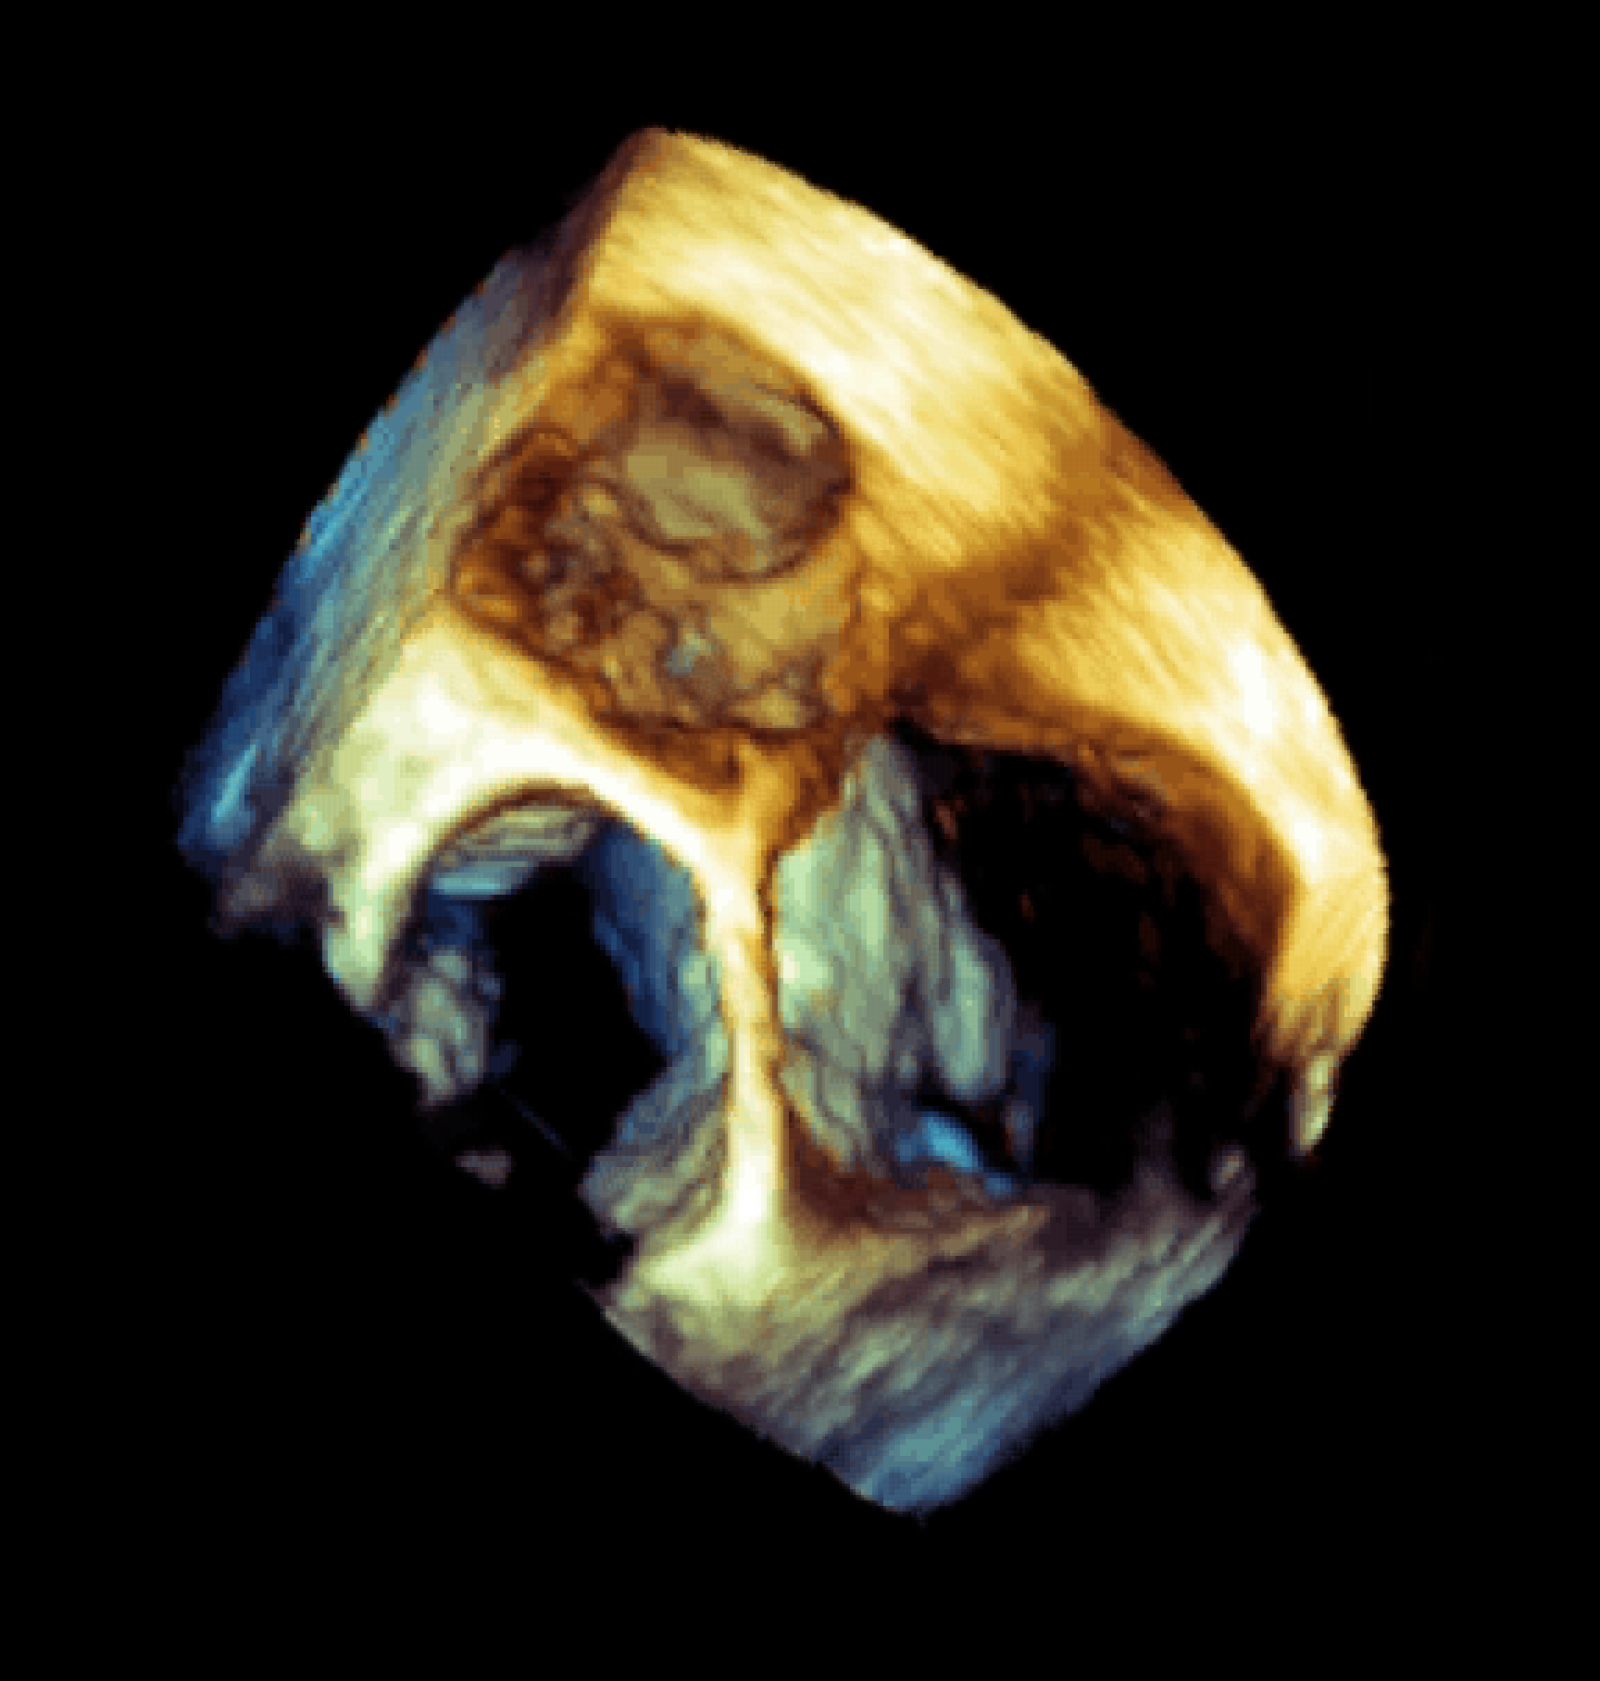

Centrum komplexní péče o vrozené srdeční vady v dospělosti vzniklo  v roce 2015  díky spolupráci  Centra kardiovaskulární a transplantační chirurgie s Interní kardiologickou klinikou Fakultní nemocnice  Brno a nabízí zcela komplexní péči o dospělé nemocné s vrozenou srdeční vadou. Portfolia jednotlivých pracovišť se navzájem doplňují.  Centrum poskytuje ambulantní sledování pacientů se všemi typy vrozených srdečních vad, neinvazivní a invazivní diagnostiku včetně transesofageální echokardiografie s využitím 3D zobrazení.  Centrum kardiovaskulární a transplantační chirurgie Brno provádí operace, reoperace a  intervenční výkony u vrozených srdečních vad a současně se věnuje chirurgické léčbě pokročilého srdečního selhání vč. implantace mechanických srdečních podpor a transplantace srdce ( Tým lékařů , seznam prováděných operačních a intervenčních výkonů).  V rámci Interní kardiologické kliniky FN Brno poskytuje invazivní  řešení arytmií ( radiofrekvenční ablace, kardiostimulace vč. resynchronizační léčby), některé intervence (uzávěry defektů septa síní) , organizaci nekardiálních operací a péči o gravidní včetně porodu probíhají v rámci Interní kardiologické kliniky FN Brno.   Návaznost na kardiologii dětského věku je zajištěna spoluprací s Fakultní dětskou nemocnicí v Brně.  Ambulantní péče probíhá na obou klinikách paralelně.